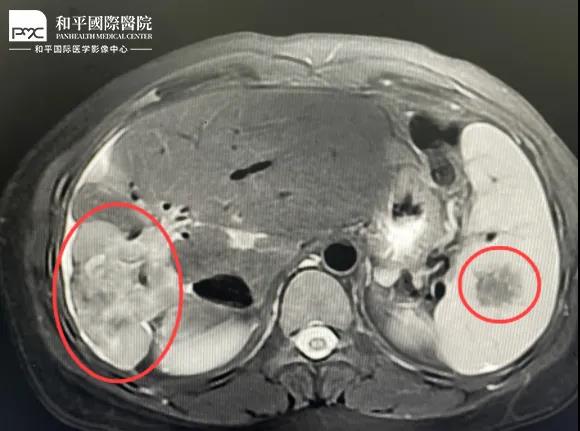

檢查結果對于這家人而言猶如晴天霹靂,經(jīng)核磁共振等相關檢查,當?shù)蒯t(yī)生懷疑是肝癌,建議手術治療。悲痛中,家人們對這樣的結果表示無法接受,想要多去幾家醫(yī)院看看,為了進一步確診,王小姐來到我院醫(yī)學影像中心進行檢查,事情竟發(fā)生了戲劇性反轉。

根據(jù)影片分析,結合王小姐有系統(tǒng)性紅斑狼瘡的病史,長期服用激素,免疫力低下,近期又有低熱盜汗的癥狀,影像中心執(zhí)行主任侯文杰初步判斷王小姐是得了肝結核,并不是肝癌!

由于肝結核是臨床非常少見的病例,單靠影像診斷是很難診斷正確的,在侯主任的建議下,王小姐做了穿刺活檢,診斷結果的確是肝結核。